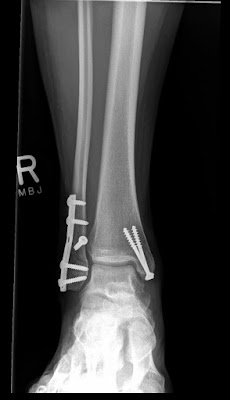

If you remember, I did derby in 2009. And I loved it. And this happened:

And that, I didn't love so much. So after lots of time not walking, and lots of time trying to walk like a normal human being, I've recently started skating again. And it's not pretty. It could be that I'm scared that the above could happen again. It also could be that I'm waaay outta shape (those Fatty McFatty thighs I've talked so highly about). Most likely, it's a combination of the both. But I'm trying, and that's what counts, right?

X-Ray courtesy of X-ray machine circa 2009